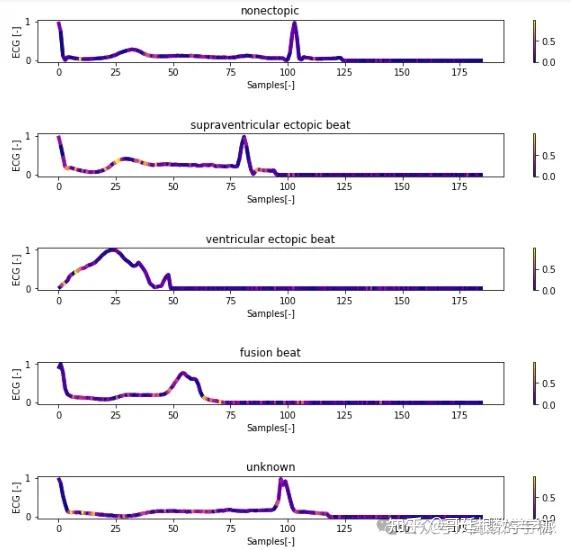

一维神经网络的特征可视化分析-以心电信号为例(Python,Jupyter Notebook)

包括Occlusion sensitivity方法,Saliency map方法,Grad-CAM方法